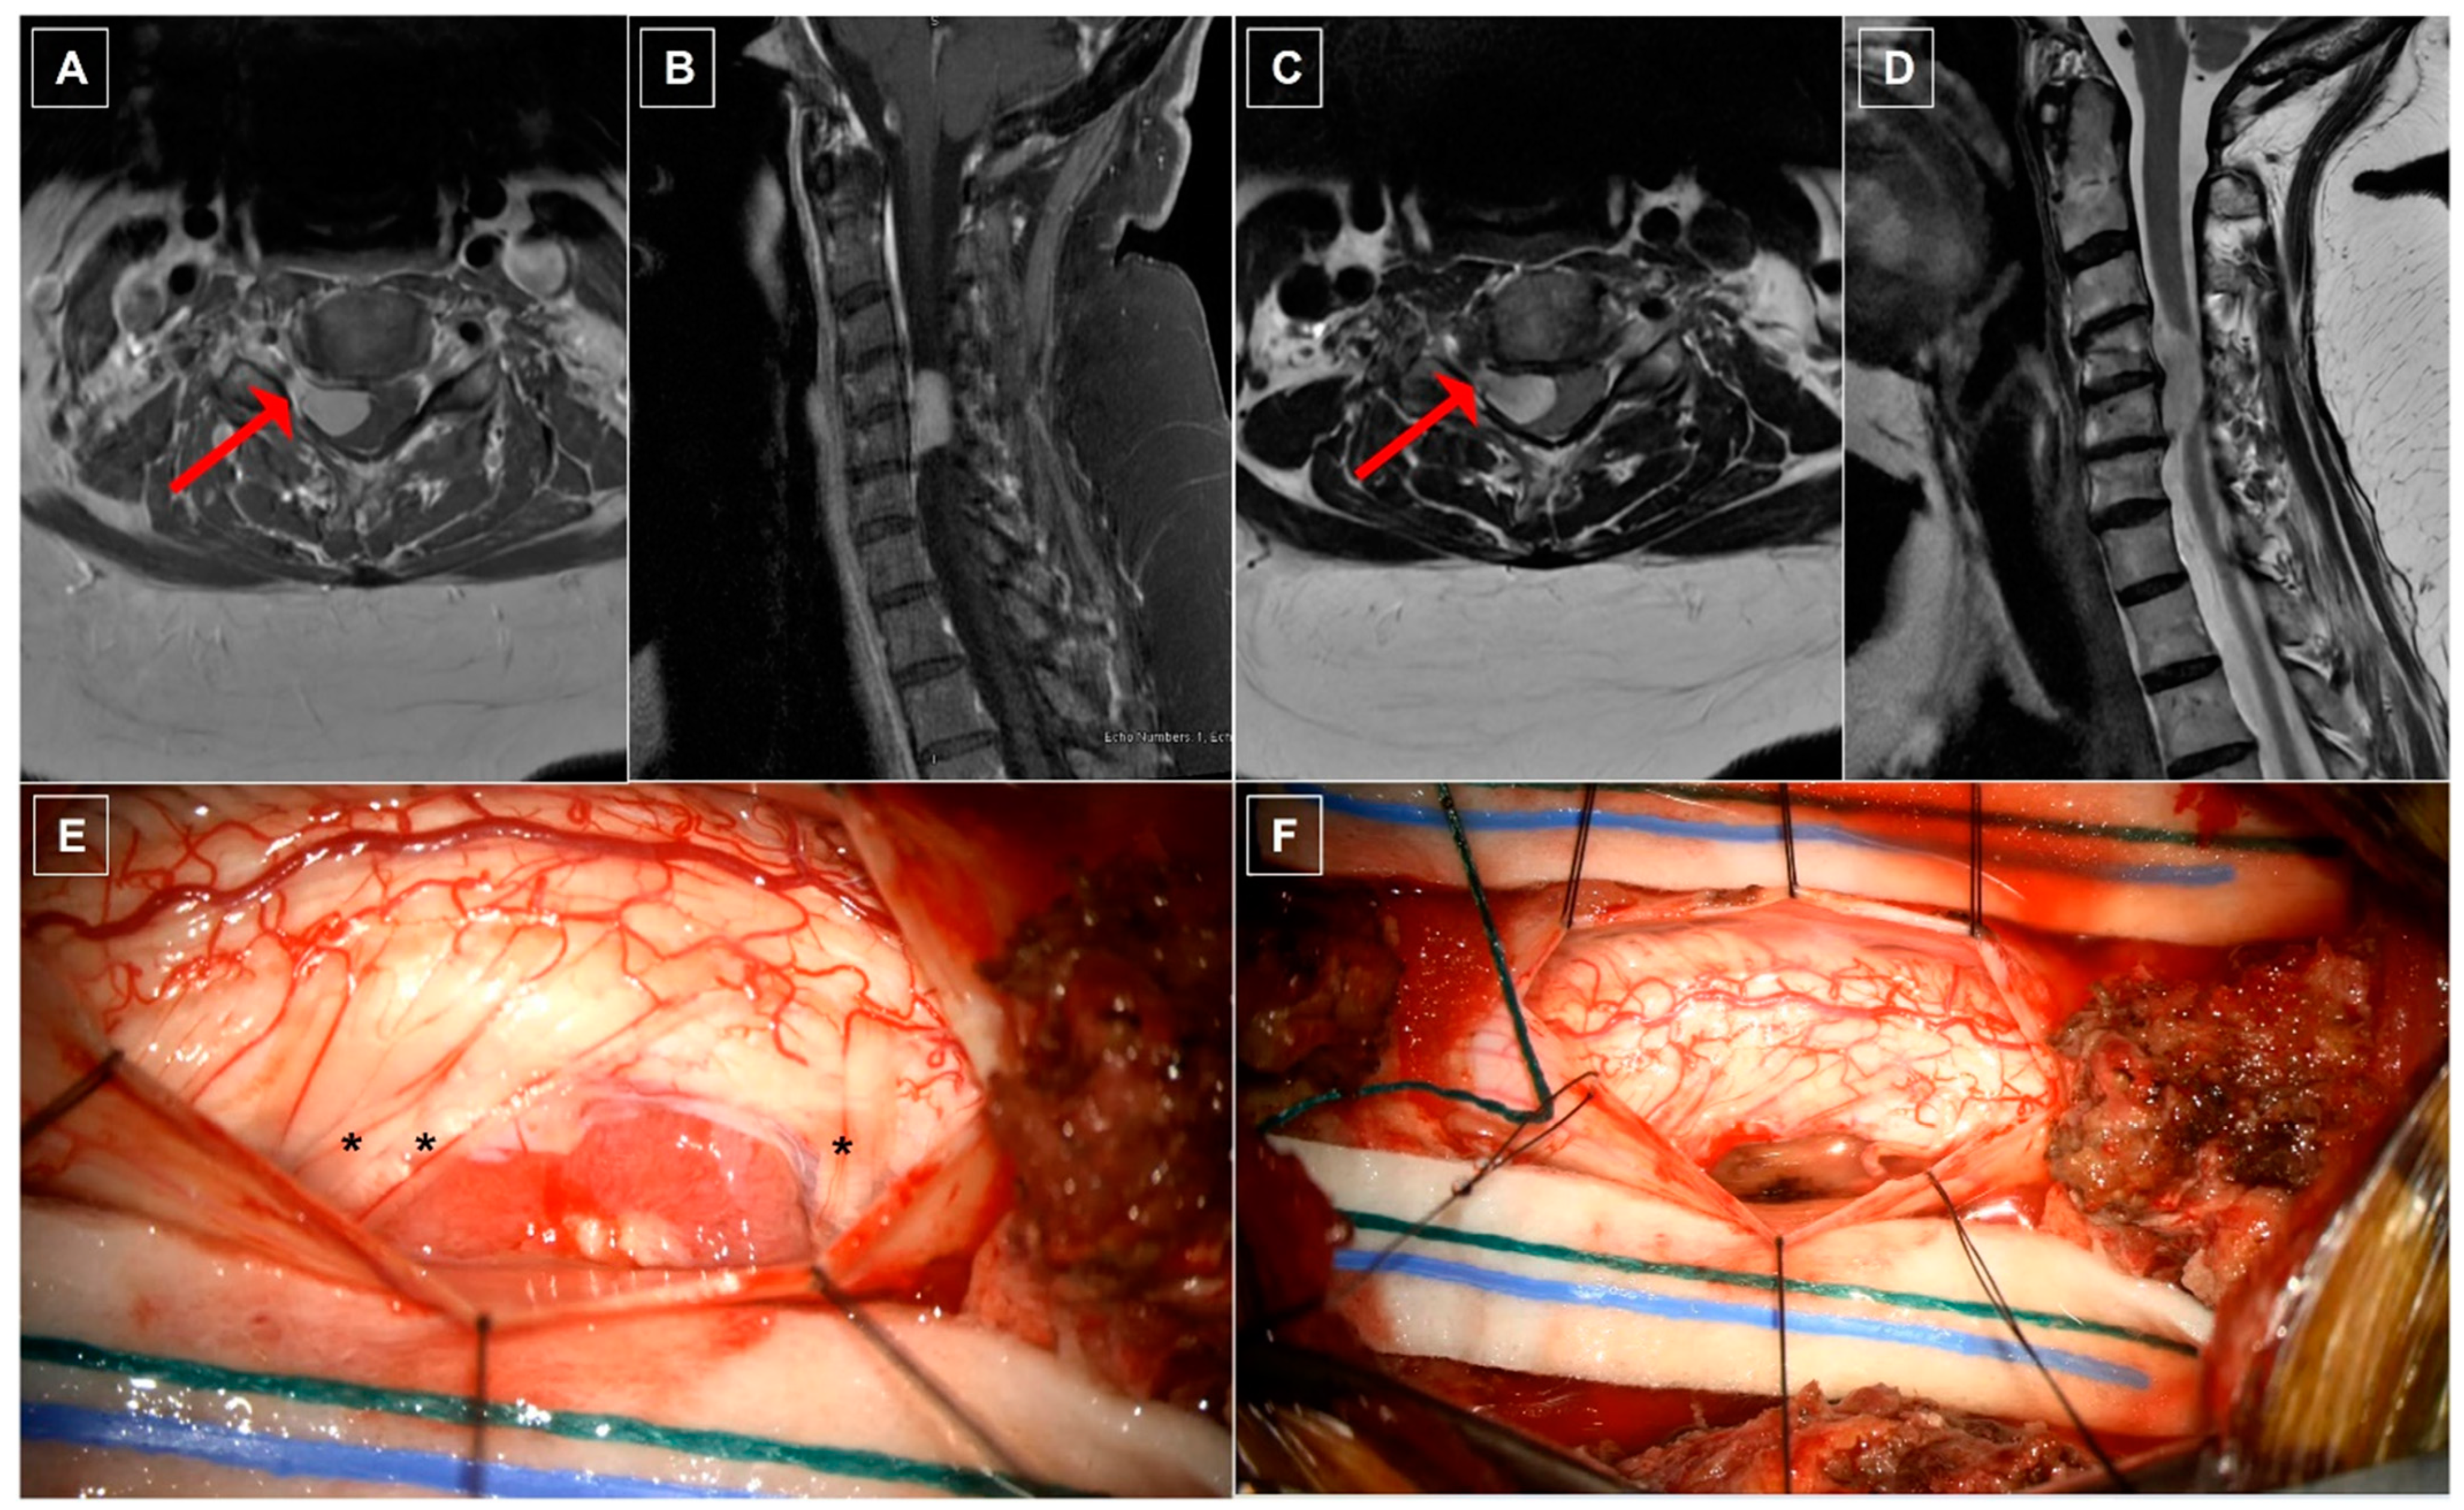

8.1. Case One: Dorsolateral Thoracic Meningioma